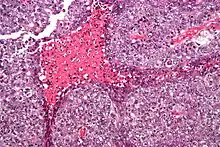

| Micrograph of an embryonal carcinoma showing its typical features - prominent nucleoli, marked nuclear atypia, necrosis, and nuclear overlap. H&E stain. | |

The microscopic features include: indistinct cell borders, mitoses, a variable architecture (tubulopapillary, glandular, solid, embryoid bodies - ball of cells surrounded by empty space on three sides), nuclear overlap, and necrosis.